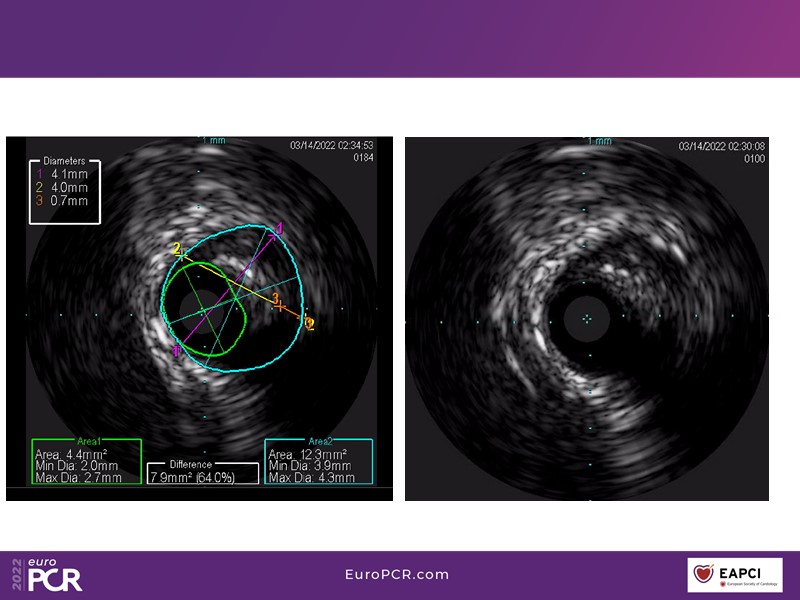

Alexandre Abizaid, Marco Valgimigli, Fazila Malik, Luca Testa, Patrick W. Serruys, Damiano Regazzoli, Kumar Prathap, and Sandeep Basavarajaiah take turns in this session to discuss two innovative technologies: a stent platform with nanotechnology and a novel drug-coated balloon (DCB). These novel technologies both have unique features that could change daily practice and improve outcomes.

- To find out more about the application and mechanism of a sirolimus coated balloon for coronary artery disease treatment with case presentations in complex settings

- To understand how useful is a DES and DCB stent platform in complex coronary artery disease settings with case demonstrations and follow-up in diabetes mellitus